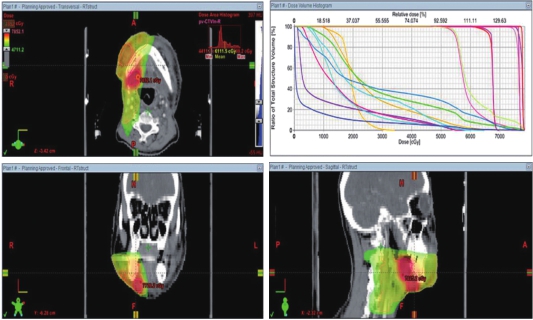

2017-02-20在我院行图像引导下调强适形放疗(IMRT),GTV-N1:2.2Gy/f,GTV-N2:2.5Gy/f,GTV-N3 :2.5Gy/f,CTV-ln:1.8Gy/f,并针对右侧颌下转移灶同步予电子线照射补量50cGy/f,共完成13f。IMRT放疗计划如图2。

图2 右侧口底、颌下病灶及区域淋巴结引流区放疗计划